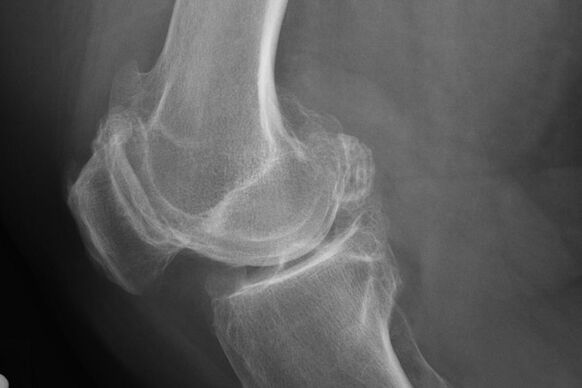

X -ray akan membantu mengenal pasti penyimpangan dalam tulang rawan.

Selepas peperiksaan, doktor menetapkan radiografi pesakit. Ini adalah kaedah utama untuk mendiagnosis arthrosis sendi lutut dari mana -mana darjah.

X -ray memberikan Doktor idea tentang perubahan yang berlaku dalam tulang rawan sendi. Walau bagaimanapun, dalam beberapa kes, peringkat awal tidak boleh ditakrifkan dalam gambar.

Sekiranya perlu, doktor boleh menetapkan laluan berulang-ulang tomografi resonans x-ray atau dikira dan magnetik.